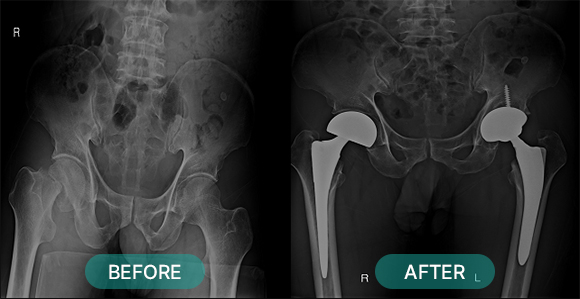

관혈적 정복이란 골절된 부위를 절개하고 뼈를 노출시켜 눈으로 직접 보면서 골절편을 정확하게 맞추는 방법으로 금속판과 나사 고정법, 핀고정법, 나사고정법, 골수 내정 고정법, 인공 관절 치환술, 외고정 기구 고정법 등등 여러 방식이 있습니다.

부위별 골절치료